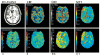

Compared to gold-standard measurements of cerebral perfusion with positron emission tomography using H(2)[(15)O] tracers, measurements with dynamic susceptibility contrast MR are more accessible, less expensive, and less invasive. However, existing methods for analyzing and interpreting data from dynamic susceptibility contrast MR have characteristic disadvantages that include sensitivity to incorrectly modeled delay and dispersion in a single, global arterial input function. We describe a model of tissue microcirculation derived from tracer kinetics that estimates for each voxel a unique, localized arterial input function. Parameters of the model were estimated using Bayesian probability theory and Markov-chain Monte Carlo, circumventing difficulties arising from numerical deconvolution. Applying the new method to imaging studies from a cohort of 14 patients with chronic, atherosclerotic, occlusive disease showed strong correlations between perfusion measured by dynamic susceptibility contrast MR with localized arterial input function and perfusion measured by quantitative positron emission tomography with H(2)[(15)O]. Regression to positron emission tomography measurements enabled conversion of dynamic susceptibility contrast MR to a physiologic scale. Regression analysis for localized arterial input function gave estimates of a scaling factor for quantitation that described perfusion accurately in patients with substantial variability in hemodynamic impairment.